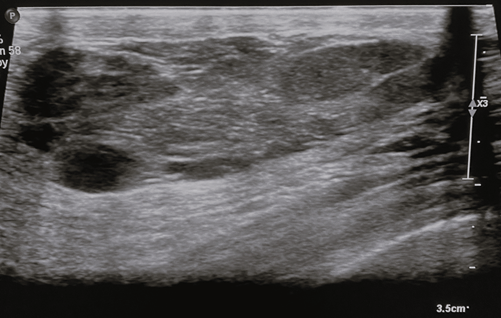

On ultrasound, the appearance of MH differs widely owing to the marked variability in the fatty and fibrous tissue constituents. They generally appear as solid, well-circumscribed, oval formations with heterogeneous echogenicity [24], aligned parallel to the skin plane (Figure 3). The lesion typically lacks hypervascularization on colour Doppler imaging and shows an echogenic or echolucent halo with posterior strengthening [2]. Incomplete pseudocapsule and tiny size with minimal fat content might make diagnosis challenging [8].

Figure 3. Breast ultrasound – breast ultrasound shows a tissue formation with the long axis parallel to the cutaneous plane, well-circumscribed, heterogeneous, with hypoechoic with hyperechoic trabeculae and posterior acoustic enhancement. Image credits: El Yousfi Z, El Mansoury FZ, El Bakkari A, Omor Y, Latib R. Breast hamartoma with synchronous contralateral breast cancer: a case report. Cureus 2024; 16(8): e66534. DOI: 10.7759/cureus.66534. Reused under the terms of the Creative Commons Attribution License CC-BY 4.0. (https://creativecommons.org/licenses/by/4.0/deed.en).